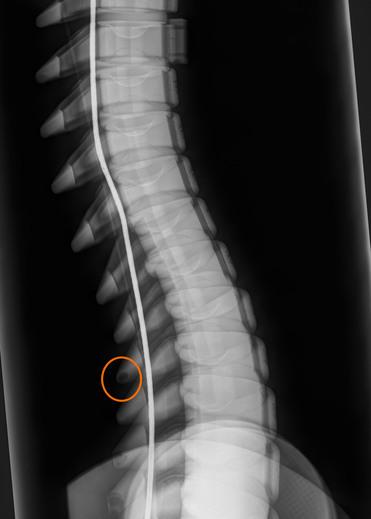

Direkt nach einem Crashtest können durch medizinisches Röntgen Beschädigungen an Knochen- und Gewebeteilen des PRIMUS-Dummys sichtbar gemacht werden. Durch diese direkten Einblicke können so Rückschlüsse auf reale Verletzungen gezogen werden und ermöglichen darüber hinaus eine Einstufung in die vereinfachte Verletzungsskala (Abbreviated Injury Scale (AIS)).

Auswertung der Röntgenbilder, PRIMUS breakable

Beispiel der technische Auswertung anhand des PRIMUS breakable

Technische Obduktion - Fotodokumentation der Verletzungen

Gutachten über die technische Obduktion (AIS-Auswertung)